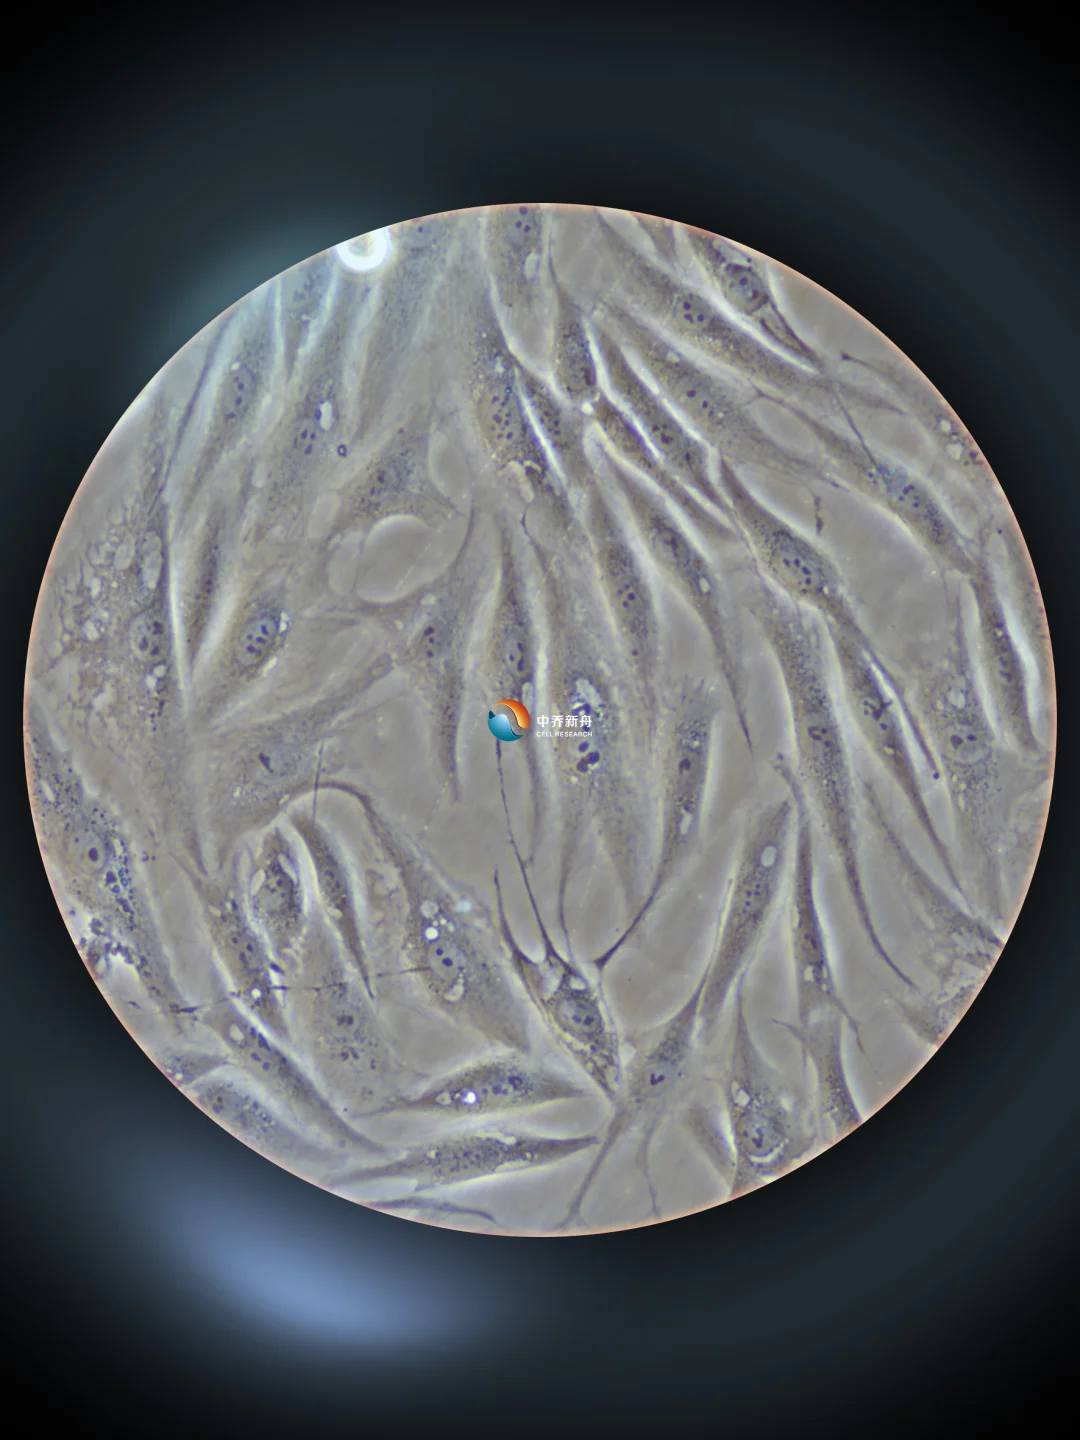

人冠状动脉平滑肌细胞,今天养这个细胞~

Human coronary smooth muscle cells 4X、10X、20X细胞影像实拍画面。